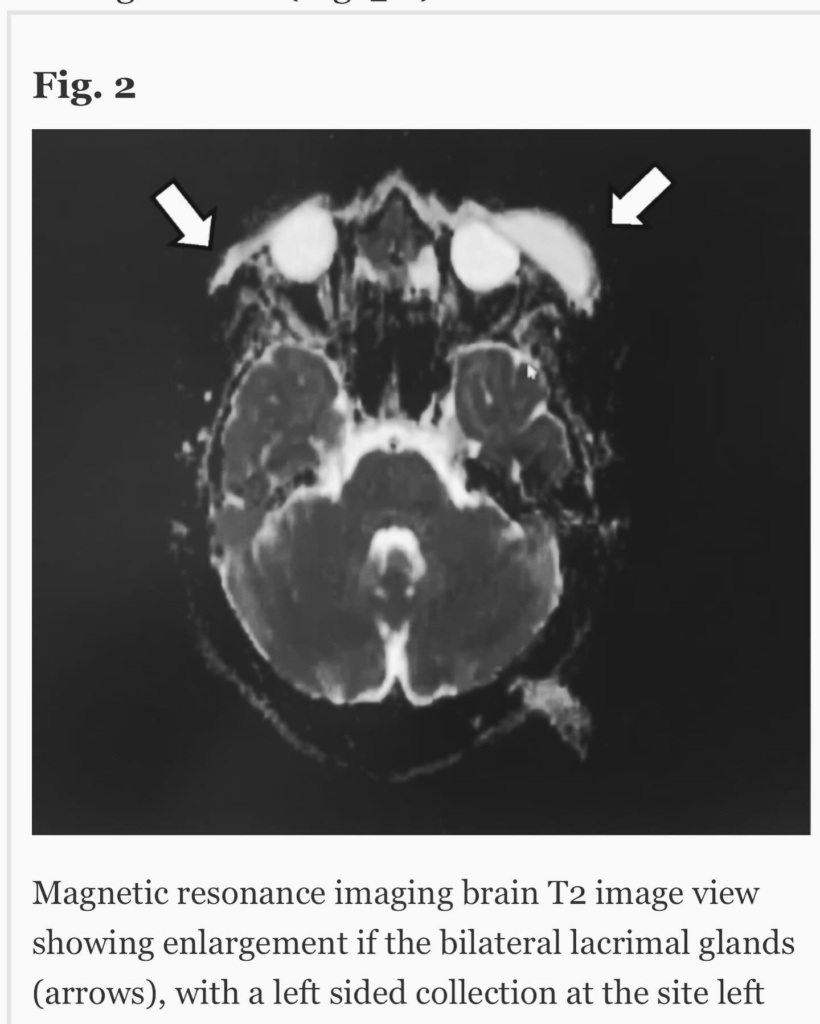

Ή μάλλον για τον τύπο που λέγεται Μάστορας. Ακούω κατά καιρούς διάφορες φήμες και έτυχε να ακούσω και τώρα κάποιες άλλες που δεν τιμούν οποίους τις διαδίδουν οπότε θα ανεβάσω μερικές φωτογραφίες από τις δύο δύσκολες τελευταίες εβδομάδες. Ο πιο σημαντικός λόγος που τις ανεβάζω είναι όμως για να μοιραστώ την ιστορία μου για την αμφοτερόπλευρη δακρυοαδενίτιδα.

Αιτία ο κοβιντ ο άτιμος… Ψάξτε το. Μπορεί και κάποιος από εσάς να υποφέρει από αυτήν αυτό τον καιρό και να μην ξέρει πώς να το διαχειριστεί.. Εγώ μπήκα στο νοσοκομείο και είχα την πιο απίστευτη γιατρό την Δήμητρα Π. να με προσέχει σε κάθε βήμα. Είμαι καλά τώρα όποτε πάμε γερά!», έγραψε χαρακτηριστικά ο Χρήστος Μάστορας.